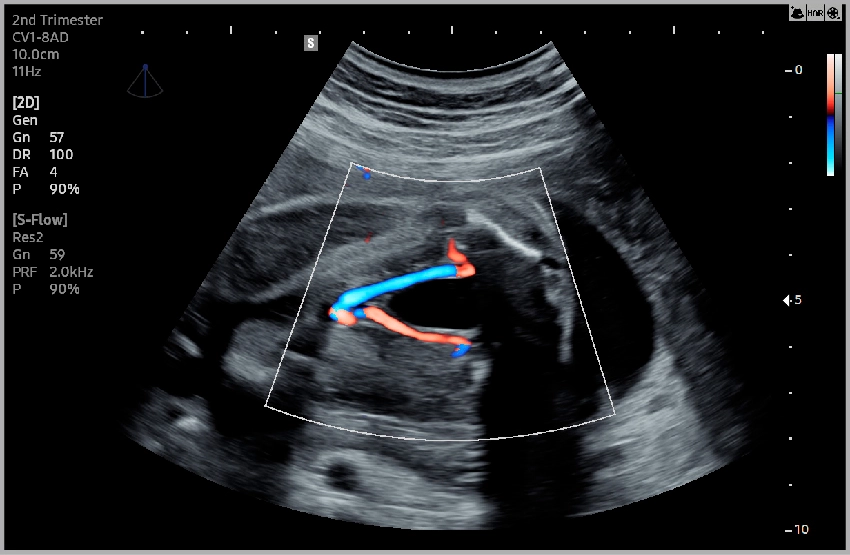

Пупочная артерия